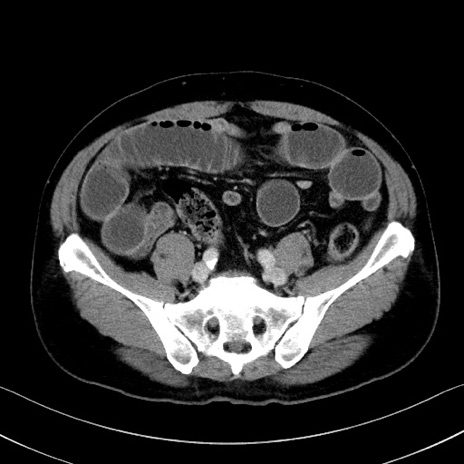

冠状断像

【症例】70歳代 男性

【主訴】腹部膨満、嘔吐

【現病歴】昨日より腹部膨満感出現。本日増悪し、仙痛出現。嘔吐あり、受診。

【既往歴】糖尿病、胆摘後

【身体所見】BP 149/80mmHg、HR 74/min、BT 35.9℃、腹部:膨満、軟、圧痛なし。腸雑音減弱あり。上腹部正中切開瘢痕あり。

【データ】WBC 13500、CRP 1.72